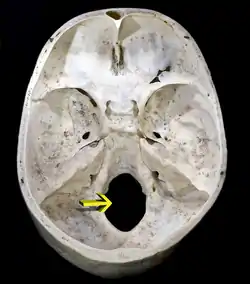

Foramen magnum

Upper surface of base of the skull. The hole indicated by an arrow is the foramen magnum